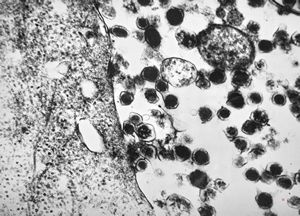

jejunum … lipid malabsorption

duodenum … lipid malabsorption